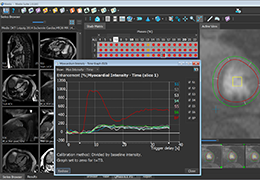

ANYTHINK 经导管主动脉瓣膜置换术分析系统